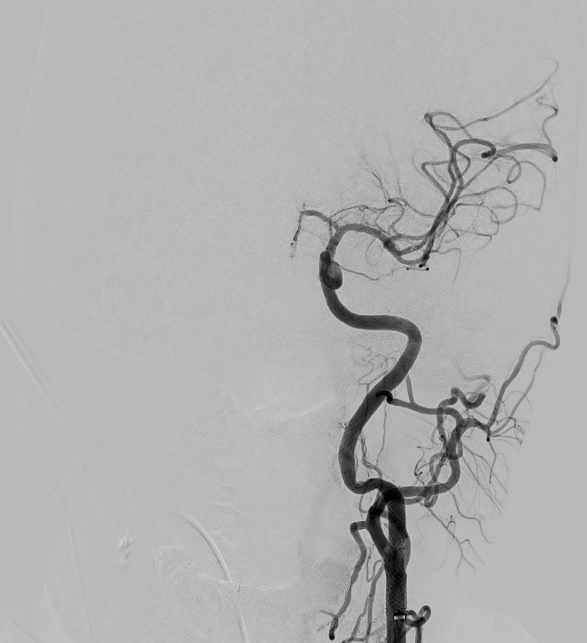

A microscopic photo illustrating carotid artery blockage

1- Carotid artery blockage in neck

a microscopic photo illustrating left middle cerebral artery clot

2- Left middle cerebral artery clot

a microscopic photo illustrating stent in carotid artery and clot removed from middle cerebral artery

3- Stent in carotid artery and clot removed from middle cerebral artery

Mechanical thrombectomy is the usual treatment when an ischemic stroke only involves one large brain-vessel blockage. It involves threading a catheter through the groin or wrist to reach the occluded vessel and remove the blood clot.

Treatment is more complex when a patient suffers a stroke with tandem occlusion. Doctors must decide between two endovascular options, treat the neck first or treat the brain first. Studies have shown benefits to both approaches:

• Neck first: For the antegrade approach, a balloon and stent are used to open the blocked carotid artery. Next, the blockage in the brain vessel is removed by threading a catheter through that freshly opened neck artery to the blood clot in the brain.

• Brain first: For the retrograde approach, the goal is to get the brain reoxygenated as quickly as possible to prevent further damage. A balloon is used to open the neck blockage just enough to get a catheter through to the brain blood clot. Once the brain vessel blockage is cleared, the doctor can back track to the ballooned neck artery and open it more firmly with additional ballooning and/or a stent.